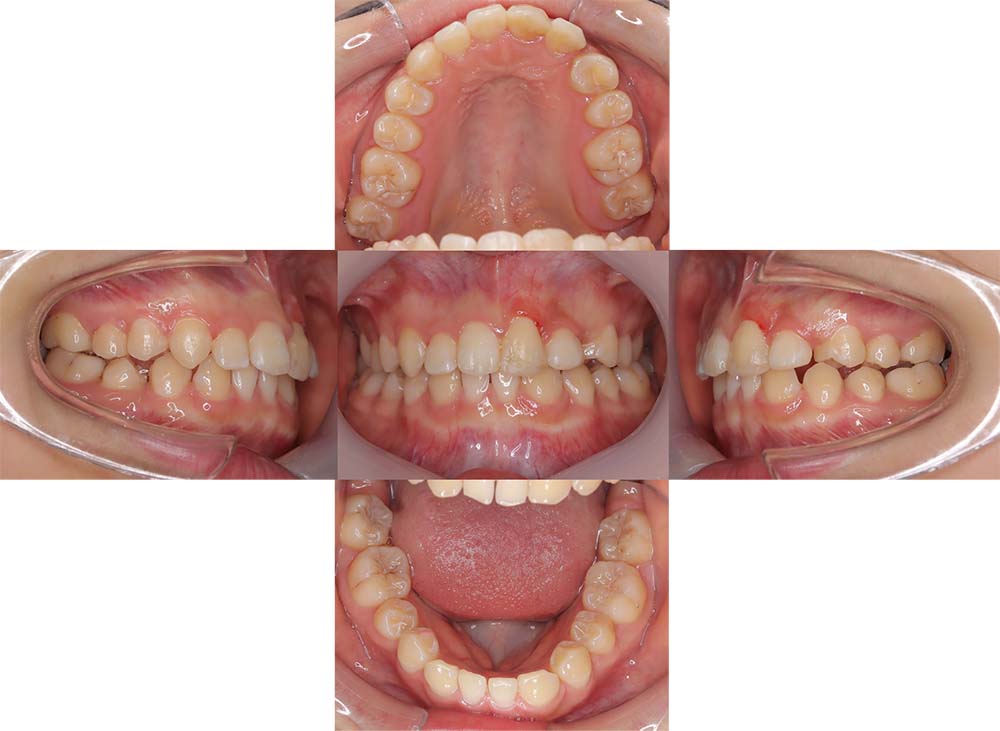

症例02

| 主訴 | 下あご顎が出ている。曲がっている。 |

| 診断名あるいは主な症状 | 反対咬合、非対称、空隙歯列、過蓋咬合 |

| 年齢/性別 | 19歳・女性 |

| 矯正ステージ | 大人の矯正治療 |

| 治療方法 | ワイヤー矯正、顎矯正手術の施行 |

| 抜歯部位/抜歯有無 | 非抜歯 |

| 治療内容 | 上下顎歯列を並べた後に顎矯正手術の施行。 |

| 費用 | 保険治療 |

| 治療期間 | 3年2ヶ月 |

| 主なリスク・副作用 | 痛み、歯根吸収、歯肉退縮、虫歯、後戻り |